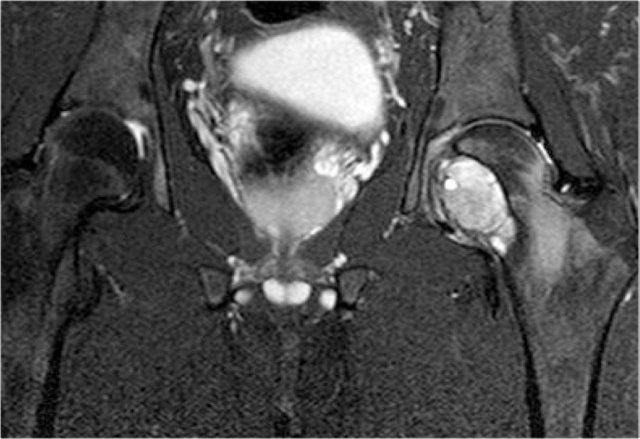

On the left a patient with a chondrosarcoma of the right acetabulum.

On the CT expansion and subtle calcifications are present.

On the coronal T2-weighted image the tumor is seen as a large lobulated mass with very high SI, which is typical for chondroid tumors.

The T1-weighted image after Gd shows typical peripheral nodular enhancement.

In the center there is no enhancement.

This is probably due to a large myxoid component. .